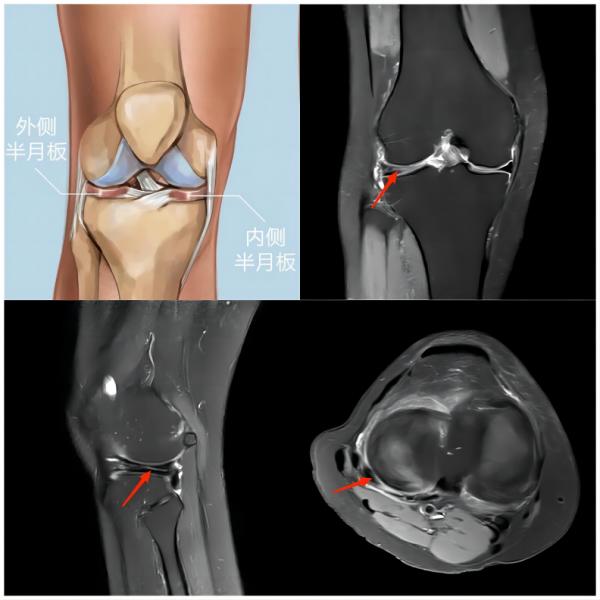

(上图为右膝外侧半月板撕裂)

常见原因:足球运动中时常发生高频次的急停、冲刺、变向等,并且还会有膝关节的屈伸、外展等动作,这些动作都会增加对膝关节的负荷,从而引发膝关节损伤。主要损伤为半月板体部撕裂、半月板根部撕裂、侧副韧带及交叉韧带的扭伤或撕裂。